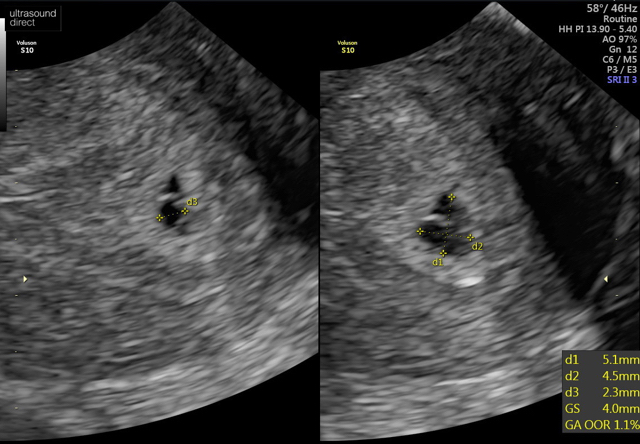

6 weeks 2 days

Couldn’t see a heartbeat but sonographer said the dates might be a little out so to go back in 2 weeks for a rescan and hopefully heartbeat will be there.